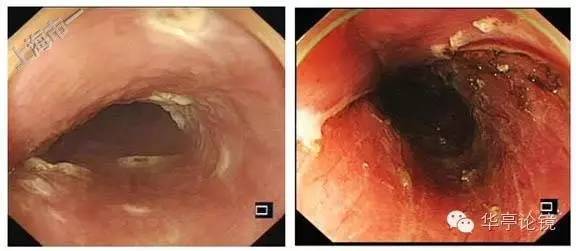

2016年7月12日于我内镜中心行食管早癌ESD术,粘膜下注射靛胭脂-甘油果糖溶液,见病灶不完全隆起,非抬举征可疑(+),将病灶周边完整剥离切除,直至固有肌层,切除过程中间病灶部分与固有肌层粘连。

ESD术切除标本见下图。

完整切除组织送检,20160719病理:(5X2.5cm,厚0.3cM,灰白组织一块):食管粘膜鳞状细胞上皮高级别上皮内瘤变,粘膜内癌形成,局部浸润至粘膜下层,病变肉眼范围约4X1.5cm,局灶瘤变鳞状上皮下查见少量腺癌成分,腺癌浸润粘膜肌层,距基底切缘及侧切缘查见腺癌(组织灼伤变形);未查见神经及脉管侵犯。

由于术后标本评估有距基底切缘及侧切缘查见腺癌,该病人追加了食管癌根治术,20160727病理: (食管一段,长6.5cm, 外径2.6cm):食管:食管切缘及食管壁组织均未见肿瘤,食管局部见炎性肉芽组织,深达肌层,偶见多核巨细胞,贲门左淋巴结(3枚)、贲门右淋巴结(2枚),胃小弯淋巴结(3枚),另送右侧第7组淋巴结(7枚)、第9组淋巴结(1枚),第10组淋巴结(纤维脂肪组织)均未见癌。